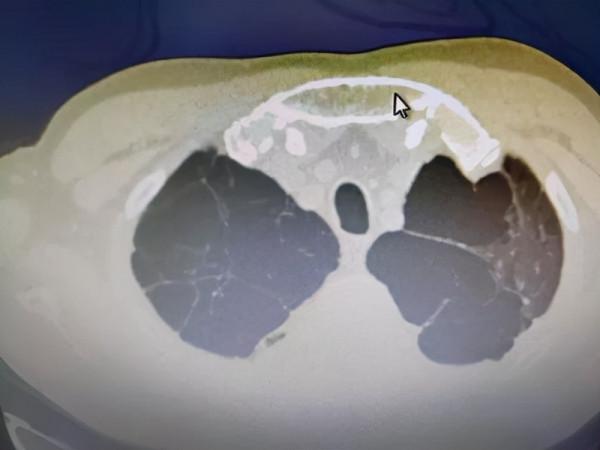

因有炎性病變,小支氣管黏膜有水腫,造成管腔部分阻塞,產生活門作用,空氣能進入肺泡而不易排出,肺泡內壓力增高,肺泡間隔逐漸因泡內壓力增加而破裂,乃形成巨大的含氣囊腔,臨床上稱之為肺大皰。

繼發於肺氣腫者,常為多發,除大皰之外,常伴有多數小皰的肺大皰本身不引起症狀,單純肺大皰的患者也常沒有症狀,有些肺大皰可經多年無改變,部分肺大皰可逐漸增大。

肺大皰的增大或在其他部位又出現新的肺大皰,可使肺功能發生障礙並逐漸出現症狀。

巨大肺大皰可使患者感到胸悶、氣短。

肺大皰突然增大破裂,可產生自發性氣胸,會引起嚴重的呼吸困難,也可出現類似心絞痛的胸痛。